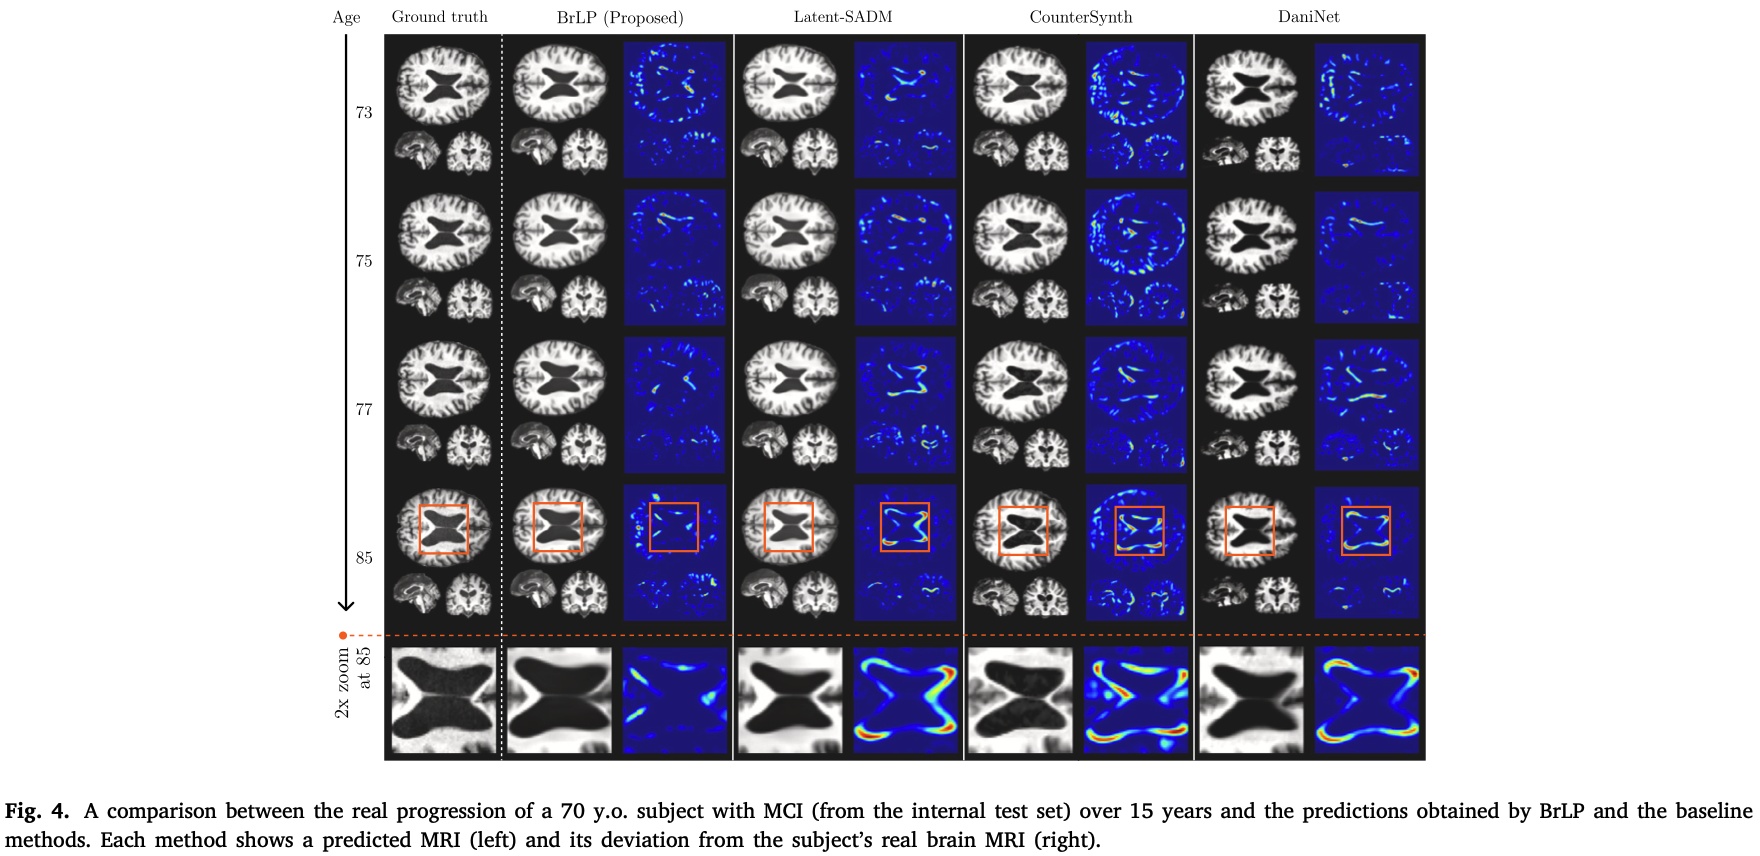

They also compare against single-frame prediction models and sequence-aware prediction models on an internal and an external dataset (see paper), but the results essentially are:

- Internal dataset: significantly beats all other methods across the board.

- External dataset: significantly better everywhere except for volumetric errors on conditional region volumes for MCI or AD patients on the Hippocampus/Amygdala regions where its on-par or slightly worse.